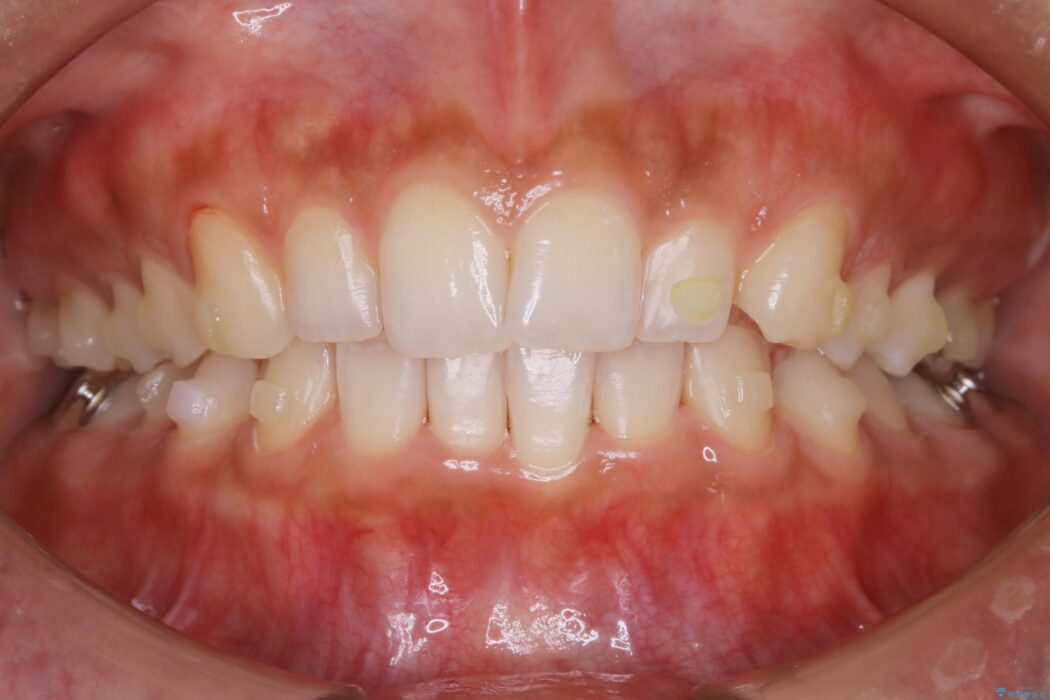

気になるガタツキと噛み合わせを改善したいとご来院されました。

下の歯列よりも上の歯列が前に出ている状態を治すため、マウスピース矯正に加え、患者様にゴムかけのご協力をいただきました。その結果、ガタつきが改善し、上下の噛み合わせが適切な位置で合うようになりました。